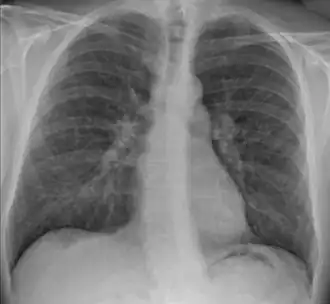

| Radiografia torácica em que se observa a nodularidade típica da sarcoidose, predominantemente no hilo pulmonar | |